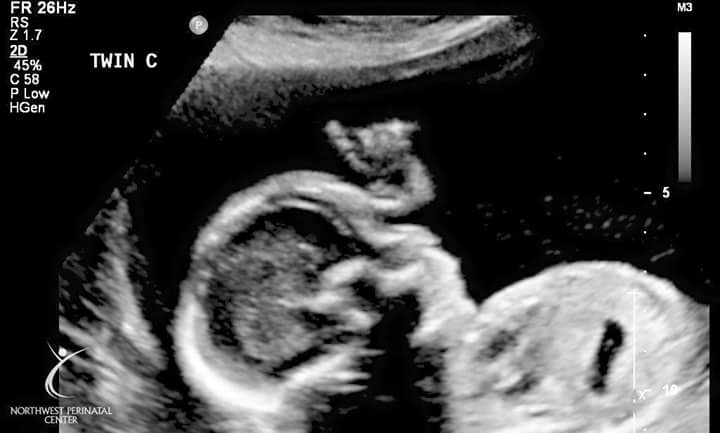

These are some pictures of the babies ultrasound and my belly at 23 weeks!

Now with these babies I kept going back and forth to all boys, to 2 boys and 1 girl. The day before my appointment I told people I'm 95% sure it's 2 boys and a girl. I thought baby A was a BOY baby B was a BOY and baby C was a GIRL. Baby C was so calm and always allowed the techs to get all their shots, and never wiggled off the monitors. So since that baby was so laid back and the other two never made things easy I figured it had to be a girl!

The tech went over each baby and showed us. Baby A is a BOY!!!! Baby B is a BOY!!! Baby C is a BOY!!! OH... MY... GOD..... We're having three more boys. I was shocked excited and couldn't believe their wasn't one girl in there. I mean we had an 80% chance that we would have mixed genders and a 12% chance of them all being the same gender. I guess we just had to beat the odds once again.